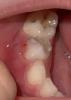

Нарыв над зубом у ребенка 6 лет: что это может быть

Дочке 6 лет . Сейчас увидела этот нарыв над зубом. Что это может быть ?

Свищ вроде

Это свищ, у моих старших так было. Удаляли зуб.

Если зуб молочный то он на удаление. Если постоянный то будут чистить

Флюс типо . Зуб вскрывать надо и чистить .